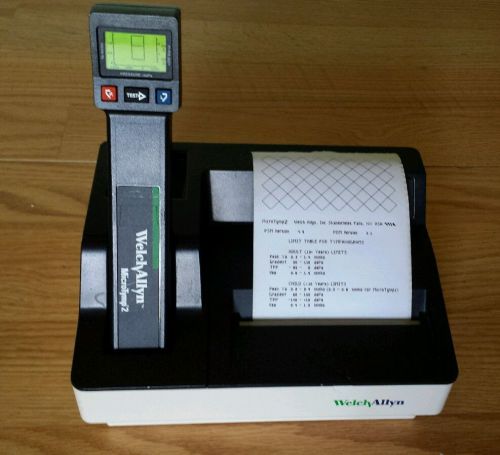

Welch Allyn Microtymp 2 Tympanometer With Printer/Charger - Nice!!